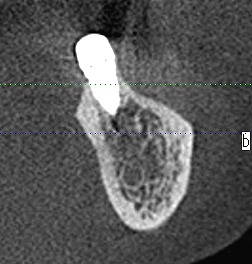

左下6番の位置になります

骨形態も悪く吸収が激しいです

7番の位置ではもっとひどいです

確かに難しい骨になっています